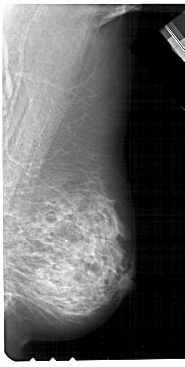

A_1211_1.RIGHT_MLO

RIGHT_MLO LINES 5491 PIXELS_PER_LINE 2761 BITS_PER_PIXEL 12 RESOLUTION 43.5 NON_OVERLAY